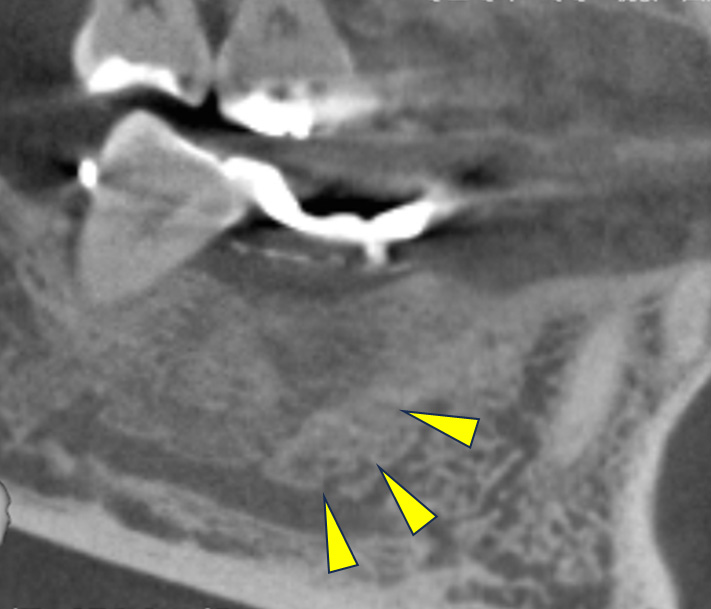

親抜歯後、歯ぐきは治癒しました。しかし、インプラント治療のためには骨が不足していました。

CT画像 -